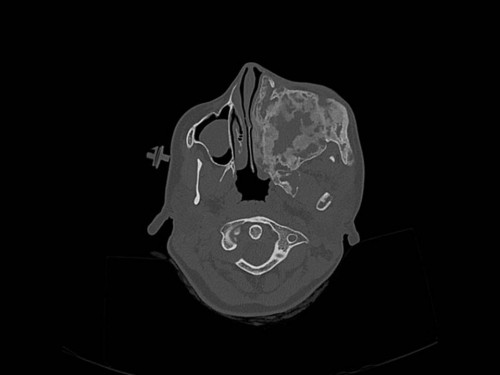

Knochendeformitäten seit der Geburt

Fall-ID: 712

ICD: M85.09

Autor*in: Sandra Klipp

Eine 16-jährige Patientin kommt in eine MKG-chirurgische Praxis zur Abklärung der weiteren Vorgehensweise bzgl. ihrer Erkrankung.

Sie betrachten die angefertigten Röntgenbilder. Welche der folgenden Röntgenbefunde ist korrekt? Ossäre Auftreibungen im Bereich …

- A… der Mandibula links.

- B… des Os frontale links.

- C… des Os zygomaticum links.

- D… des Os temporale links.

- EAlle genannten Aussagen sind korrekt.

Bildgebung - OPAN 2004